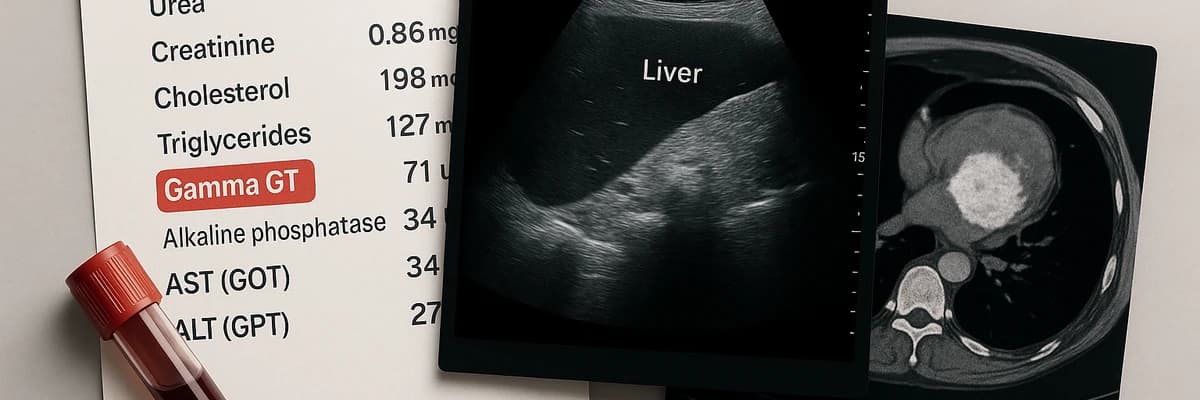

Quels examens demander en cas de Gamma GT élevé ?

Gamma GT élevé : analyses, imagerie et suivi médical. Découvrez les examens indispensables pour identifier la cause et agir sur votre santé.